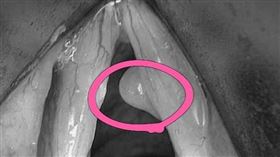

「聲音沙啞」是警訊!伴隨3症狀恐是腫瘤

燒聲超過7天不單純!3症狀恐是息肉、腫瘤

小小年紀「菸酒嗓」 醫:1種可能是菜花

聲音沙啞超過2周好不了 醫師一看竟是癌

日抽80根菸 他燒聲變喉癌第3期

無法飆高音、沙啞...恐聲帶長囊腫